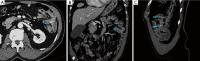

Figure 3

A 72-year-old male presenting with anemia and no active demonstrable source of bleeding on upper or lower endoscopy. CT enterography demonstrated multiple dilated vessels in the wall of the jejunum (A: axial CTE image; B: coronal CTE image; C: sagittal CTE image) on the enteric phase (arrows) which were also demonstrated on the subsequently performed capsule endoscopy compatible with jejunal vascular malformations, presumed to be the cause for occult GI bleed.